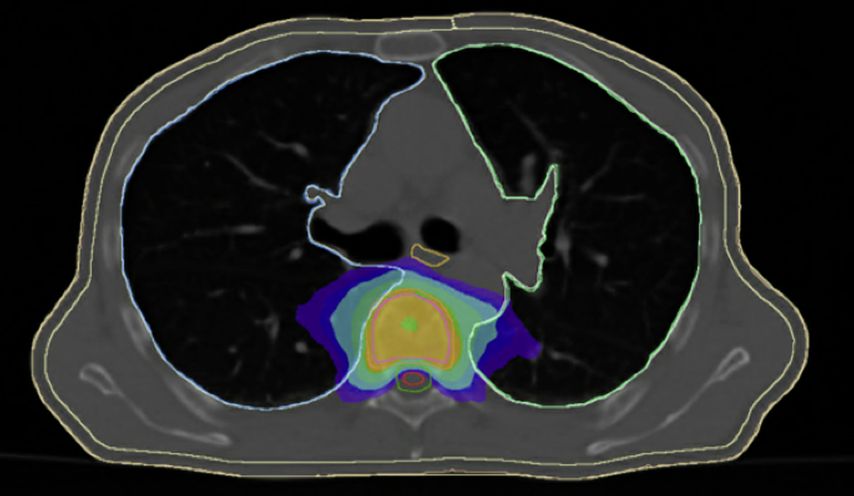

Durch eine stereotaktische Radiotherapie mit Aussparung des Myelons (Abb. 1.) besteht die Möglichkeit, im oligometastasierten Setting eine tumorablative Strahlendosis zu applizieren. In kurativer Intention ist dies postoperativ bei inkomplett resezierten Knochenmetastasen sinnvoll. Gegenüber einer Standardbestrahlungstechnik sollte die Hochpräzisionsradiotherapie vor allem bei erneuten Bestrahlungen zur Rückenmarksschonung unabhängig vom Fraktionierungsschema präferiert werden.